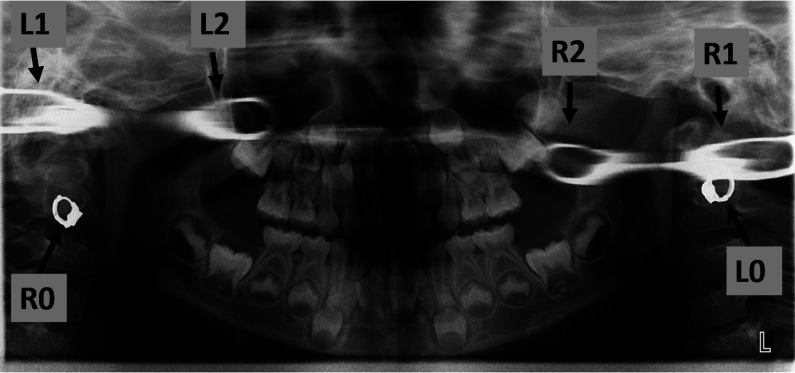

Purpose: This report presents a unique case featuring real, ghost, and pseudo-ghost images on the panoramic radiograph of a patient wearing earrings. It also explains the formation of these images in an easy-to-understand manner.

Material and methods: One real image and two ghost images appeared on each side of a panoramic radiograph of a patient wearing earrings on both sides. Of the two ghost images on each side, one was considered a typical ghost image and the other was considered a ghost-like real image (pseudo-ghost image). The formation zones of the real, double, and ghost images were examined based on the path and angles of the X-ray beam from the Planmeca ProMax. To simulate the pseudo-ghost and typical ghost images on panoramic radiography, a radiopaque marker was affixed to the right mandibular condyle of a dry mandible, and the position of the mandible was adjusted accordingly.

Results: The center of rotation of the Planmeca ProMax extended beyond the jaw area, and the area of double image formation also reached beyond the jaw. The radiopaque-marked mandibular condyle, situated in the outwardly extending area of double image formation, exhibited triple images consisting of real, double (pseudo-ghost), and ghost images. These findings helped to explain the image formation associated with the patient's earrings observed in the panoramic radiograph.